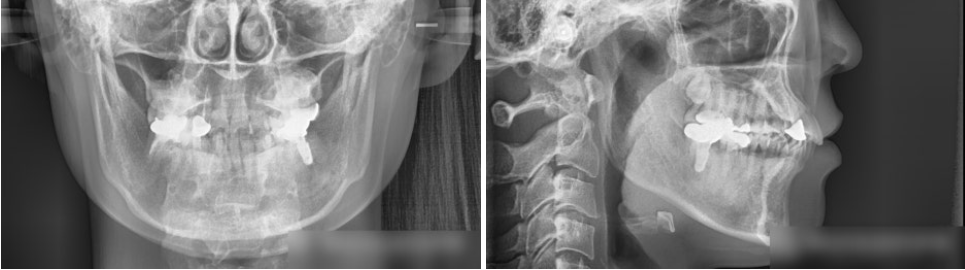

골격적인 검진을 진행한 결과

다행히 정중선도 중앙에 잘 맞고 있는 편에 속했으며

돌출입 경향은 발견되지 않았습니다.

상악의 각도가 조금 과도하긴 하지만

크게 문제가 될 정도는 아니였죠^^